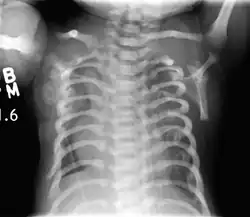

CXR of a newborn with asphyxiating thoracic dysplasia. Note the short ribs.

Asphyxiating thoracic dysplasia (ATD), also known as Jeune syndrome, is a rare inherited bone growth disorder (autosomal recessive skeletal dysplasia) [1] that primarily affects the thoracic region. It was first described in 1955 by the French pediatrician Mathis Jeune.[2] Common signs and symptoms can include a narrow chest, short ribs, shortened bones in the arms and legs, short stature, and extra fingers and toes (polydactyly). The restricted growth and expansion of the lungs caused by this disorder results in life-threatening breathing difficulties; occurring in 1 in every 100,000-130,000 live births in the United States.[1][3]

Jeune syndrome is a rare genetic disorder that affects the way a child's cartilage and bones develop. It begins before the child is born and primarily affects the child's rib cage, pelvis, arms and legs.[5] Usually, problems with the rib cage cause the most serious health problems for children with Jeune syndrome. Their rib cages (thorax) are smaller and narrower than usual, which inhibits the child's lungs from developing fully or expanding when they inhale. The child may breathe rapidly and shallowly. They may have trouble breathing when they have an upper or lower respiratory infection, like pneumonia. Breathing trouble can range from mild to severe. In some children, it is not noticeable, aside from fast breathing; however, in others, breathing problems can be fatal. About 60% to 70% of children with this condition die from respiratory failure as babies or young children. Children with Jeune syndrome who survive often develop problems with their kidneys, and over time they may experience kidney failure.[2] As a result, few children with Jeune syndrome live into their teen years. Children with Jeune syndrome have a form of dwarfism. They are short in stature, and their arms and legs are shorter than most people's.[6]

Jeune syndrome is a rare autosomal recessive ciliopathy.[7] This diagnosis is grouped with other chest problems called thoracic insufficiency syndrome (TIS). Diagnosis of Jeune syndrome can be made as early as before birth if signs and symptoms are apparent on an ultrasound; however, diagnosis after birth usually occurs through X-rays and genetic testing, such as the tests found on the Genetic Testing Registry (GTR).[8]